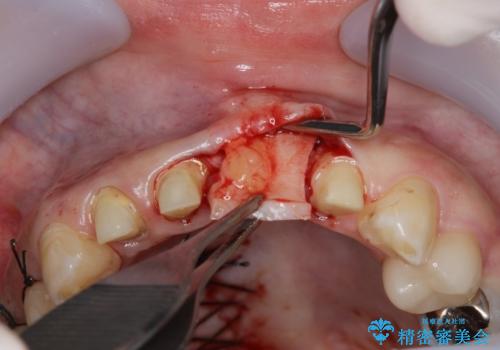

左側の前歯には他院で埋入されたポジションの悪いインプラント補綴により歯冠長の長いクラウンが装着されており、感染による排膿も認められこのまま審美性を改善するのは難しい状態です。

不良インプラントを除去し最終的にブリッジによる補綴で審美性の改善を行うこと、その準備として骨の造成・歯肉の移植による歯の欠損部顎堤のボリュームを維持・増大を計画します。

感染したインプラントからは排膿が間欠的に認められ、掻爬・除去が検討されうるような状況でした。

より審美的な改善を強く求められたため、インプラントを除去し可及的に欠損部顎堤を増大したのちブリッジによる審美改善を行いました。